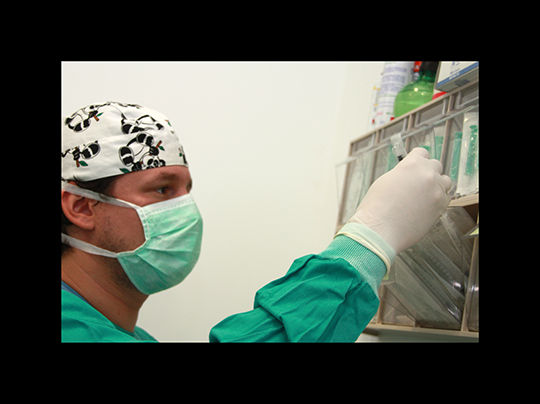

cirugía

En CLINICAN las intervenciones quirurgicas se realizan bajo anestesia inhalatoria, y el animal se encuentra monitorizado en todo momento, lo que ofrece una mayor seguridad.